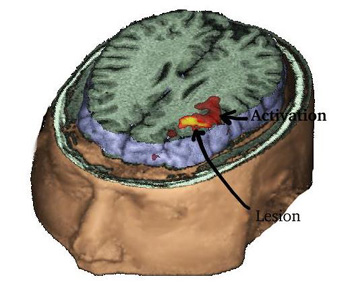

Caso 3

Niño diestro de 13 años de edad con epilepsia del lóbulo temporal. Se detectó un oligodendroglioma multiquístico en el lóbulo temporal izquierdo (flechas negras). Se indicó una IRM para llevar a cabo un mapeo de las áreas del lenguaje antes de la resección quirúrgica.

Una IRMf tridimensional muestra la masa en el polo temporal izquierdo. La activación se obtuvo mediante un paradigma de "tarea de repetición" (burbujas de color amarillo, anaranjado y rojo). La relación entre la lesión y las áreas del habla se muestra magníficamente.